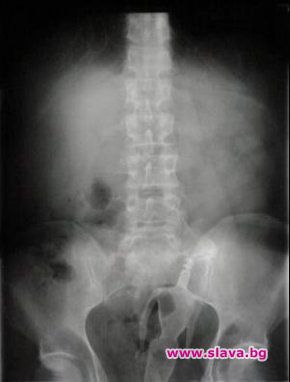

Вадят кукла Барби от ануса на даскал

Именно в семейното жилище в областния град се разиграла драмата – дългопазената хомосексуална наклонност на даскала лъснала, когато той бил заварен в брачното ложе крещящ от болка и със стърчащи от дупето чифт кукленски крака в розови токчета. Първоначално двамата опитали сами да изтеглят кукличката от задника му, но след появата на кръв и нетърпима болка се принудили да викнат бърза помощ. Преди около година, през август 2011, лекар от Пирогов разказа и други подобни истории за заседнали странни предмети – вибратори, дезодоранти, дървени чукчета от хаванчета за чесън, шишета. Най-странно обаче било, когато дежурен екип бил посечен от реплика на младо момче: Извинявайте, но си напъхах една дюля в задника.

В повечето случаи предметите се вадят по неоперативен начин. Понякога обаче се налагат и по-сериозни мерки - например ако се окажете с флакон от пяна за бръснене в дупето и твърдите пред лекарите, че сте се подхлъзнал в банята и сте се нанизал на него, какъвто случай имаше в търновско преди време. Още по-сложна е ситуацията с дамите естествоизпитателки, търсещи всевъзможни начини да увеличат сексуалното си удоволствие.